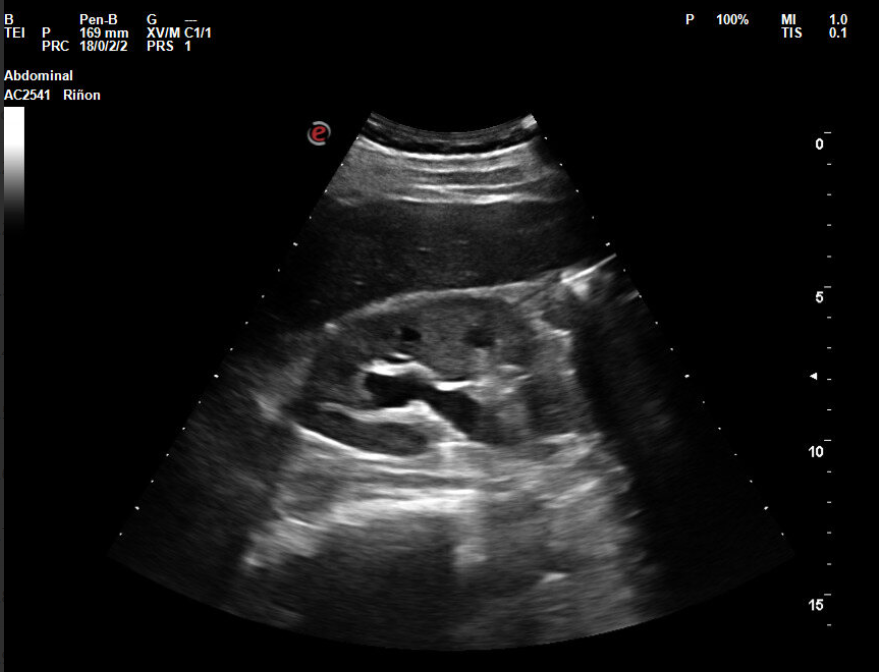

Hallazgos ecográficos

En la ecografía objetivamos discreta dilatación calicial y dilatación del uréter derecho. Se visualiza vejiga de características normales, con jet ureteral bilateral presente. No se objetivan litiasis. Tras explicar signos y síntomas de alarma por los que acudir a urgencias se decide solicitar estudio con ecografía preferente para revalorar y verificar resolución del cuadro, y realizar consulta preferente a urología.

Cólico renal derecho. Hidronefrosis leve. Las imágenes de ecografía obtenidas en el hospital son concordantes con las del centro de salud. También la actitud terapéutica elegida ya que se opta por una actitud conservadora a la espera de respuesta de urología.